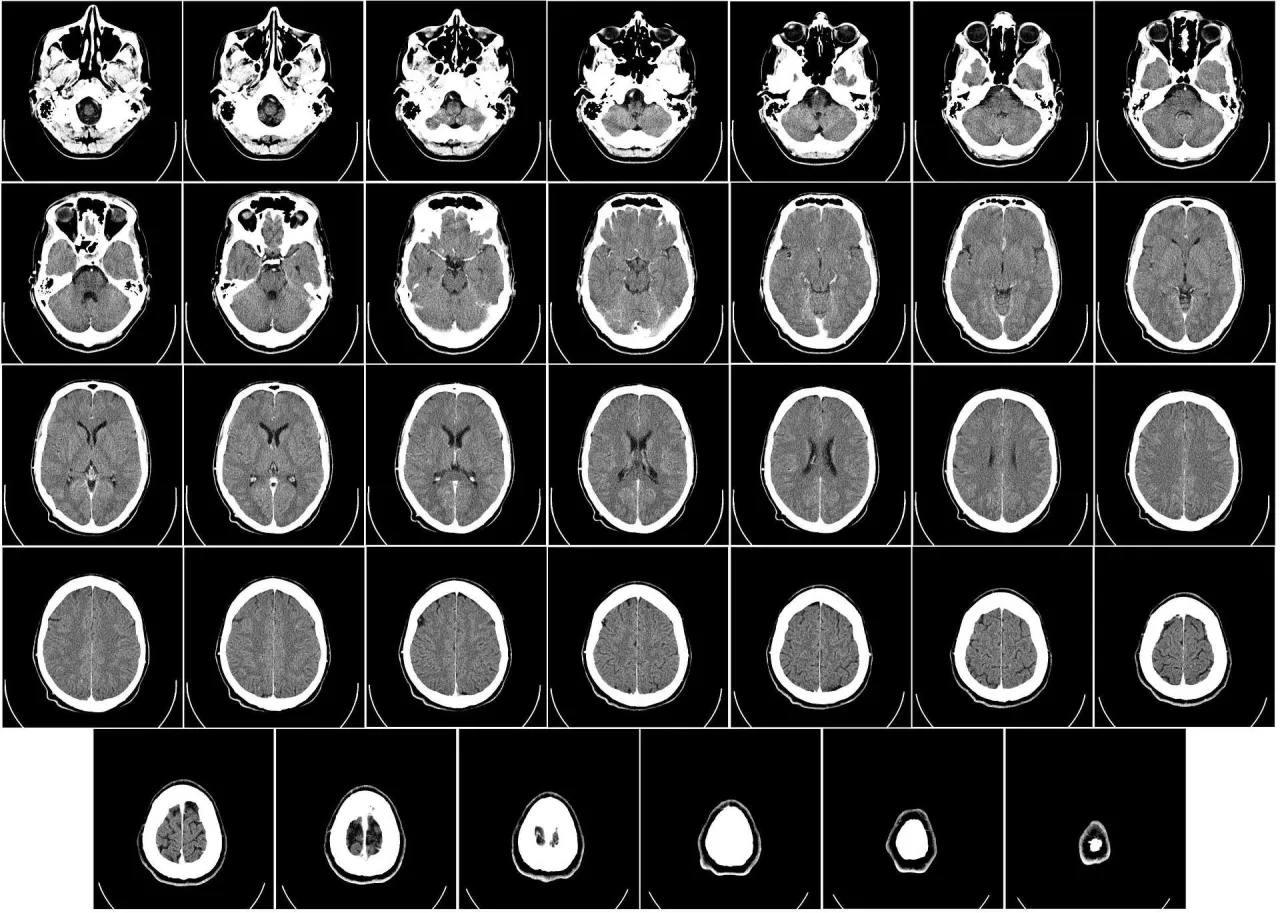

Tomografia komputerowa (TK) głowy to zaawansowana metoda obrazowania medycznego, która wykorzystuje promieniowanie rentgenowskie do tworzenia szczegółowych, przekrojowych obrazów mózgu, kości czaszki i innych struktur wewnątrzczaszkowych. Dla mnie, jako osoby zajmującej się diagnostyką, jej rola w neurologii jest fundamentalna. Dzięki szybkości wykonania i szerokiej dostępności, TK głowy stała się niezastąpionym narzędziem, szczególnie w sytuacjach nagłych, gdzie każda minuta ma znaczenie dla zdrowia i życia pacjenta.

Zasada działania tomografu komputerowego jest fascynująca, choć na pierwszy rzut oka może wydawać się skomplikowana. Wyobraźmy sobie, że tomograf to taka specjalna "pralka" z dużą, okrągłą dziurą, przez którą przejeżdża stół z pacjentem. Wewnątrz tej "dziury" znajduje się lampa rentgenowska, która emituje promienie, oraz detektory, które te promienie odbierają. Gdy promienie rentgenowskie przechodzą przez ciało, są w różnym stopniu pochłaniane przez tkanki kości pochłaniają je mocniej niż tkanki miękkie, takie jak mózg. Detektory zbierają te informacje, a następnie komputer przetwarza je w szczegółowe obrazy przekrojowe. To trochę jak krojenie bochenka chleba na cienkie kromki, aby zobaczyć, co jest w środku z tą różnicą, że tomograf robi to wirtualnie, bezinwazyjnie i w trójwymiarze.